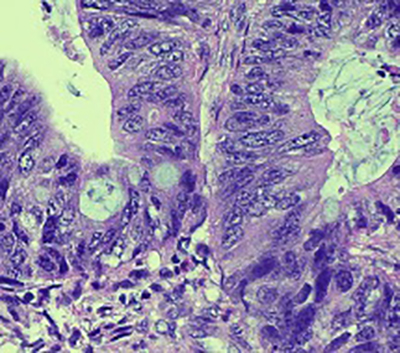

Histopathologic examination showed fragmented specimen containing adenocarcinoma, characterized by relatively well formed glands with cribriform glands in some areas. The epithelial cells were relatively uniform with basally oriented nuclei and intracytoplasmic mucin was present in a subset of cells. Some areas contained areas of necrotic cellular debris within the lumens of the neoplastic glands. No areas of non-atypical endometrial hyperplasia or endometrial intraepithelial neoplasia were identified. There were fragments of leiomyomas in the background. Immunohistochemical analysis demonstrated the adenocarcinoma cells to be positive for CK20, CDX-2, SATB-2 (patchy), MUC2 (patchy) and CEA. They were negative for CK7, PAX-8, GATA-3, ER, PR, Vimentin and hrHPV in-situ. The p16 and MUC6 showed rare positive neoplastic cells, and p53 demonstrated a wild type pattern. Mismatch repair proteins were intact. The combined morphologic and immunohistochemical features support and adenocarcinoma with an enteric/gastrointestinal phenotype. The case was finalized as moderately differentiated adenocarcinoma with intestinal/enteric phenotype. In the absence of any notable conventional endometrioid adenocarcinoma or precursor endometrial proliferation, the differential diagnosis included a metastasis (likely from colorectal origin or other sites which may acquire an intestinal phenotype, and an unusual primary endometrial carcinoma with pure intestinal metaplasia/differentiation. Additional workup to exclude extrauterine primary sites was recommended.

Fig. 1 Adenocarcinoma embedded in endometrial stroma (A and B). Adenocarcinoma with dirty necrosis (C) and intracytoplasmic mucin (D). The malignant cells are negative for CK-7 (E) and positive for CK-20 (F), CDX-2 (G), SATB-2 (H).